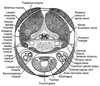

Describe how the neck is organized in terms of fascial planes.

The neck is compartmentalized in two main divisions of fascia: the superficial cervical fascia and the deep cervical fascia.

The superficial cervical fascia includes subcutaneous tissue and envelops the muscles of facial expression. It is continuous with the superficial musculoaponeurotic system (SMAS) and extends inferiorly to involve the platysma.

The deep cervical fascia is divided into superficial, middle, and deep layers.

- The superficial layer invests parotid and submandibular glands, muscles of mastication, trapezius, sternocleidomastoid, and forms the stylomandibular ligament.

- The middle layer is composed of two divisions: the visceral division invests the larynx, pharynx, trachea, esophagus, thyroid, and parathyroid; the muscular division invests the strap muscles.

- The deep layer is composed of two divisions as well: the prevertebral divisionenvelops the paraspinal muscles and vertebrae; the alar division lies atop the prevertebral layer and covers the sympathetic trunk. The carotid sheath represents the confluence of the deep layers of the deep cervical fascia